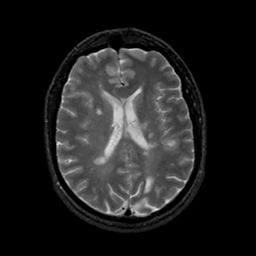

MR Study #17, July 7, 1991 -- Slice #30